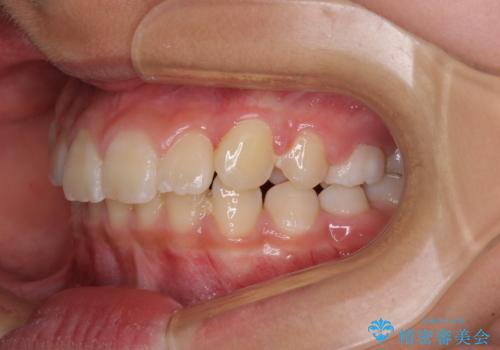

今後残っている乳歯が抜け、永久歯が萌出してくるため、調整可能なリンガルアーチを用いて保定を行っています。

12歳臼歯が萌出するまで経過観察を行い、すべての歯が萌出した後に、全顎矯正治療(Ⅱ期治療)を行っていきます。